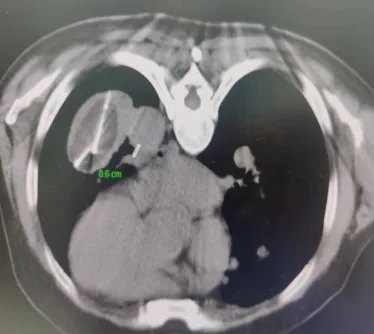

术中消融

患者病灶位于左下肺,大小8.5*5.6cm,患者俯卧位CT扫描定位,左下肺可见肿块影,局部麻醉后,按照手术设计穿刺路径,分别将阳极针、阴极针经皮穿刺进入病灶,通过冷消融4个循环、电解消融1个循环后,CT扫描可见肺内病灶坏死明显,手术2小时后顺利结束。术后病人无不适症状,3天后好转出院。